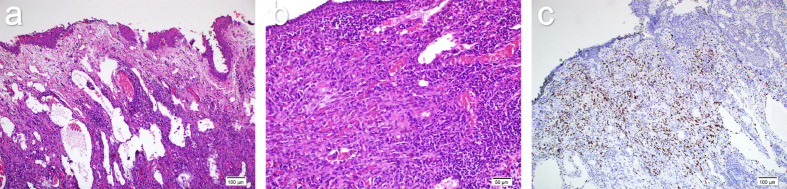

Kaposi sarcoma (KS) is a vascular neoplasm caused by human herpes virus-8 and is commonly associated with immunocompromised states such as acquired immunodeficiency syndrome. While ocular involvement is rare and typically occurs in human immunodeficiency virus (HIV)-positive patients, it can exceptionally present in HIV-negative, immunocompetent individuals. This report presents two cases of conjunctival KS: One in an HIV-positive patient and another in an HIV-negative patient. The patients were diagnosed and followed up at Istanbul Medeniyet University Göztepe Prof. Dr. Süleyman Yalçın City Hospital. Written informed consent was obtained from the patients for the preparation of this case report. A 35-year-old HIV-positive male with a history of cutaneous and genital KS presented with a painless, reddish, hemorrhagic mass on the left inferior fornix and a firm mass on the lower eyelid. Surgical excision with adjuvant cryotherapy and amniotic membrane transplantation was performed. One year postoperatively, no recurrence or new lesions were observed. A 76-year-old immunocompetent female presented with a painless, progressively enlarging mass in the left inferior fornix. She underwent surgical excision, adjuvant cryotherapy, and amniotic membrane transplantation. Histopathology confirmed the diagnosis of KS, and at the 1-year follow-up, no recurrence or new lesions were observed. Ocular KS, though rare, can occur in both immunocompromised and immunocompetent individuals. This report highlights the importance of considering KS in the differential diagnosis of subconjunctival hemorrhage, even in patients without underlying immunosuppressive conditions. Both cases were successfully managed with surgical excision, adjuvant cryotherapy, and amniotic membrane transplantation, with no recurrence during follow-up.